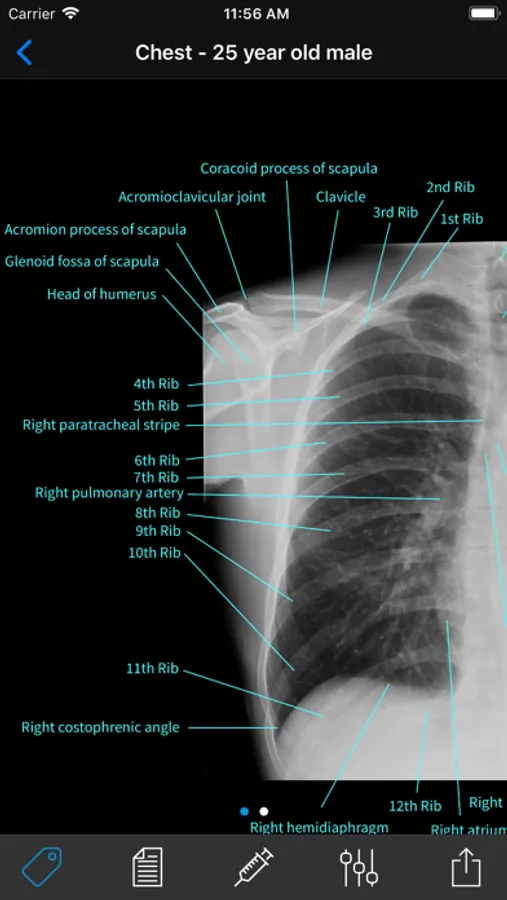

• A complete radiographic atlas of human anatomy

• 2000+ high resolution x-rays spanning patients of all ages (all x-rays have been read by board-certified radiologists)